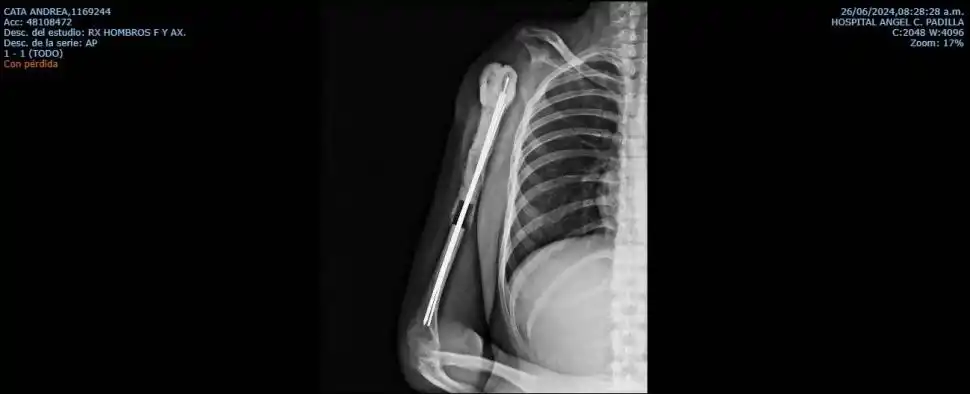

ANTES Y DESPUES. Las radiografías muestran cómo quedó el hombro de Andrea.

Al día siguiente, estuvieron nueve horas para sacar el tumor. Durante la cirugía debieron ponerle más de 10 litros de sangre. Los médicos admiten que, en un momento, estuvieron a punto de perder el brazo. Vivieron esos minutos con mucha tensión, separando nervio por nervio para afectar lo menos posible a la paciente. Luego, tuvieron que reconstruirle el húmero y todo el espacio que ocupaba el tumor y que ahora había quedado vacío. Para ello usaron cemento quirúrgico.

Los profesionales detallaron que ahora, con una rehabilitación, Andrea va a poder mover su brazo y su mano, tal vez no al 100%, pero sí podrá hacerlo. El hombro, por su parte, quedó muy limitado, ya que los músculos de esa zona se vieron demasiado afectados por el tumor. En un futuro, tendrá que hacerle otra cirugía para ponerle una prótesis.